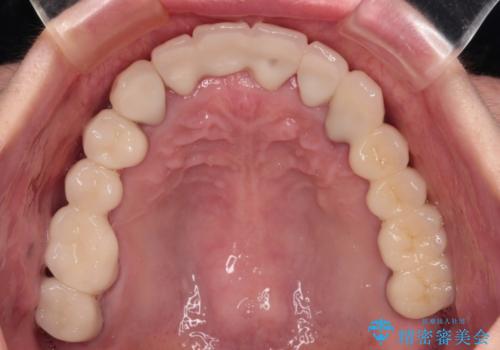

- 以前通院していた医院で、奥歯のインプラント埋入、前歯部のインビザライン矯正を行ったものの、そのまま放置してしまったとのことで来院された患者様です。

下顎前歯や上顎奥歯などをワイヤー装置により部分矯正を行い、歯列を整えた上でインプラン部分を含めてオールセラミッククラウンにて補綴治療を行うこととしました。

インプラント上の仮歯がボロボロになり、前歯に非常に負担のかかる状態であったため、早急に奥歯の仮歯を修復し、矯正治療、奥歯の補綴治療、前歯の補綴治療と順々に進めて行きました。